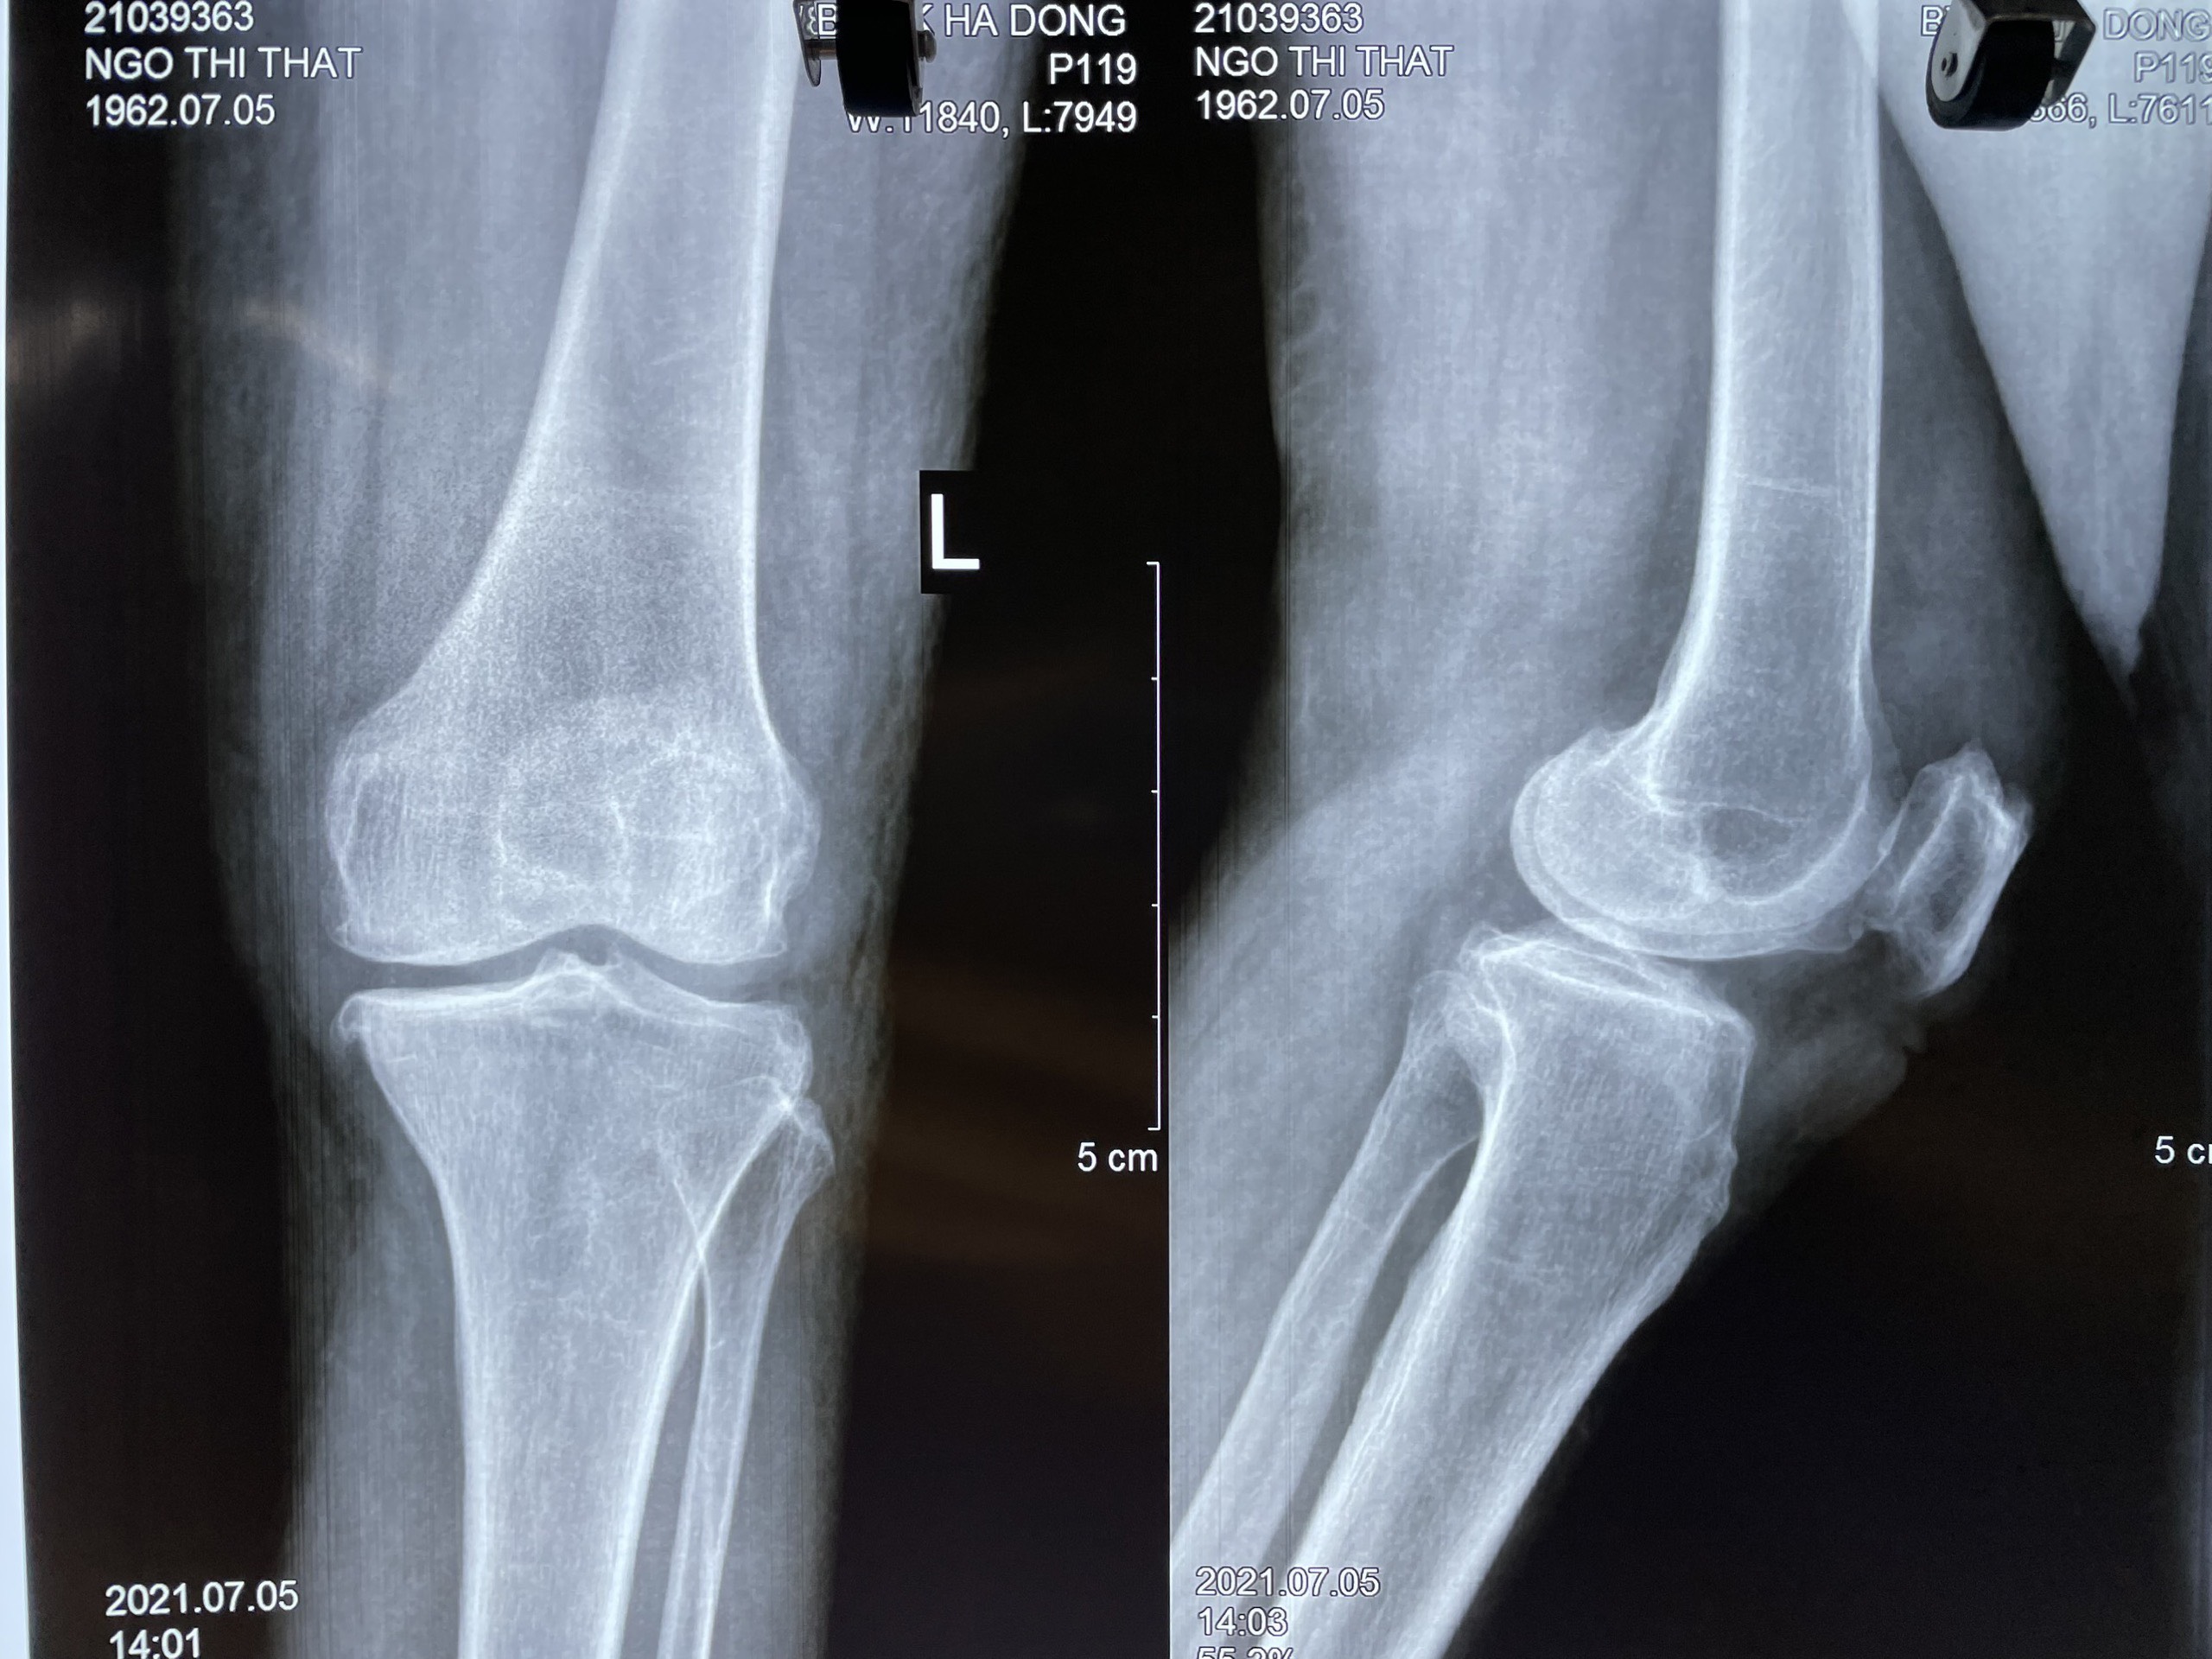

Hình ảnh x-quang 2 khớp gối sau mổ

Tại đây, các bác sĩ thăm khám lâm sàng có biểu hiện tràn dịch khớp gối mức độ vừa, biên độ vận động gối bình thường, không có mất vững gối, không có triệu chứng lâm sàng của tổn thương sụn chêm. Chụp phim Xquang thấy có tổn thương mất liên tục của xương bánh chè phía trên ngoài, siêu âm có tràn dịch khớp gối. Chẩn đoán sơ bộ bệnh lý xương bánh chè hai mảnh hai gối vì không có yếu tố chấn thương. được chụp phim cộng hưởng từ đánh giá các dây chằng, sụn chêm và sụn khớp đều thấy bình thường. Tổn thương cực trên của hai gối nghĩ đến thương tổn xương bánh chè hai mảnh.

Th.S BS Nguyễn Trọng Nghĩa cho biết: BS Phẫu thuật nội soi khớp gối là kỹ thuật hiện đại đang được áp dụng tại các bệnh viện đa khoa Hà Đông. Đây là kỹ thuật ít xâm lấn (ít gây tổn thương thêm cho người bệnh), trong và sau mổ người bệnh ít đau đớn, giảm nguy cơ nhiễm trùng, rút ngắn thời gian nằm viện, giảm chi phí điều trị, nhanh chóng phục hồi và trở lại cuộc sống, sinh hoạt bình thường. Đặc biệt với kỹ thuật này vết nội nhỏ khoảng 3cm nhanh liền seo, còn kỹ thuật nội soi truyền thông vết nội soi dài 15 đến 20 cm và lâu liền sẹo).

Sau 4 ngày sau phẫu thuật, bệnh nhân đã hết đau, đã bắt đầu tập đi. Dự kiến, sau 2 tuần bệnh nhân có thể tự đi mà không cần đến dụng cụ hỗ trợ